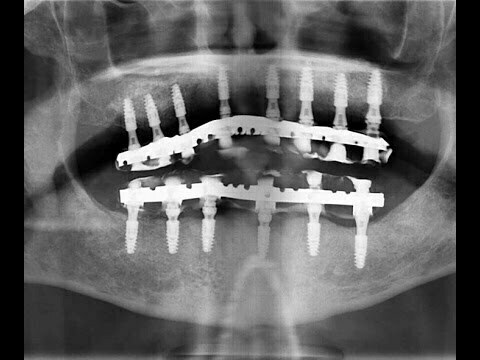

Chirurgie Dr Lambert MCI bimaxillaire en 2h30